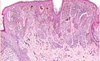

Identify

Seborrheic Keratosis

- well demarcated

- mushroom epidermis

- horn cysts(spaces in the tumor filled with keratin)

- benign

- regular looking cells

- wouldn’t see a lot of mitosis

What is this?

Mitoses and atypia in seborrheic keratosis

What is this depicting?

Mitoses and atypia